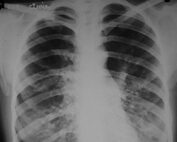

Tétano generalizado: a propósito de un caso clínico

Ana Marcela Tobías Rodríguez, MD Servicio de Pediatría, La Misericordia Clínica Internacional Introducción: El tétano es una enfermedad aguda causada por una toxina producida por Clostridium tetanii. La enfermedad puede afectar a personas de cualquier [...]